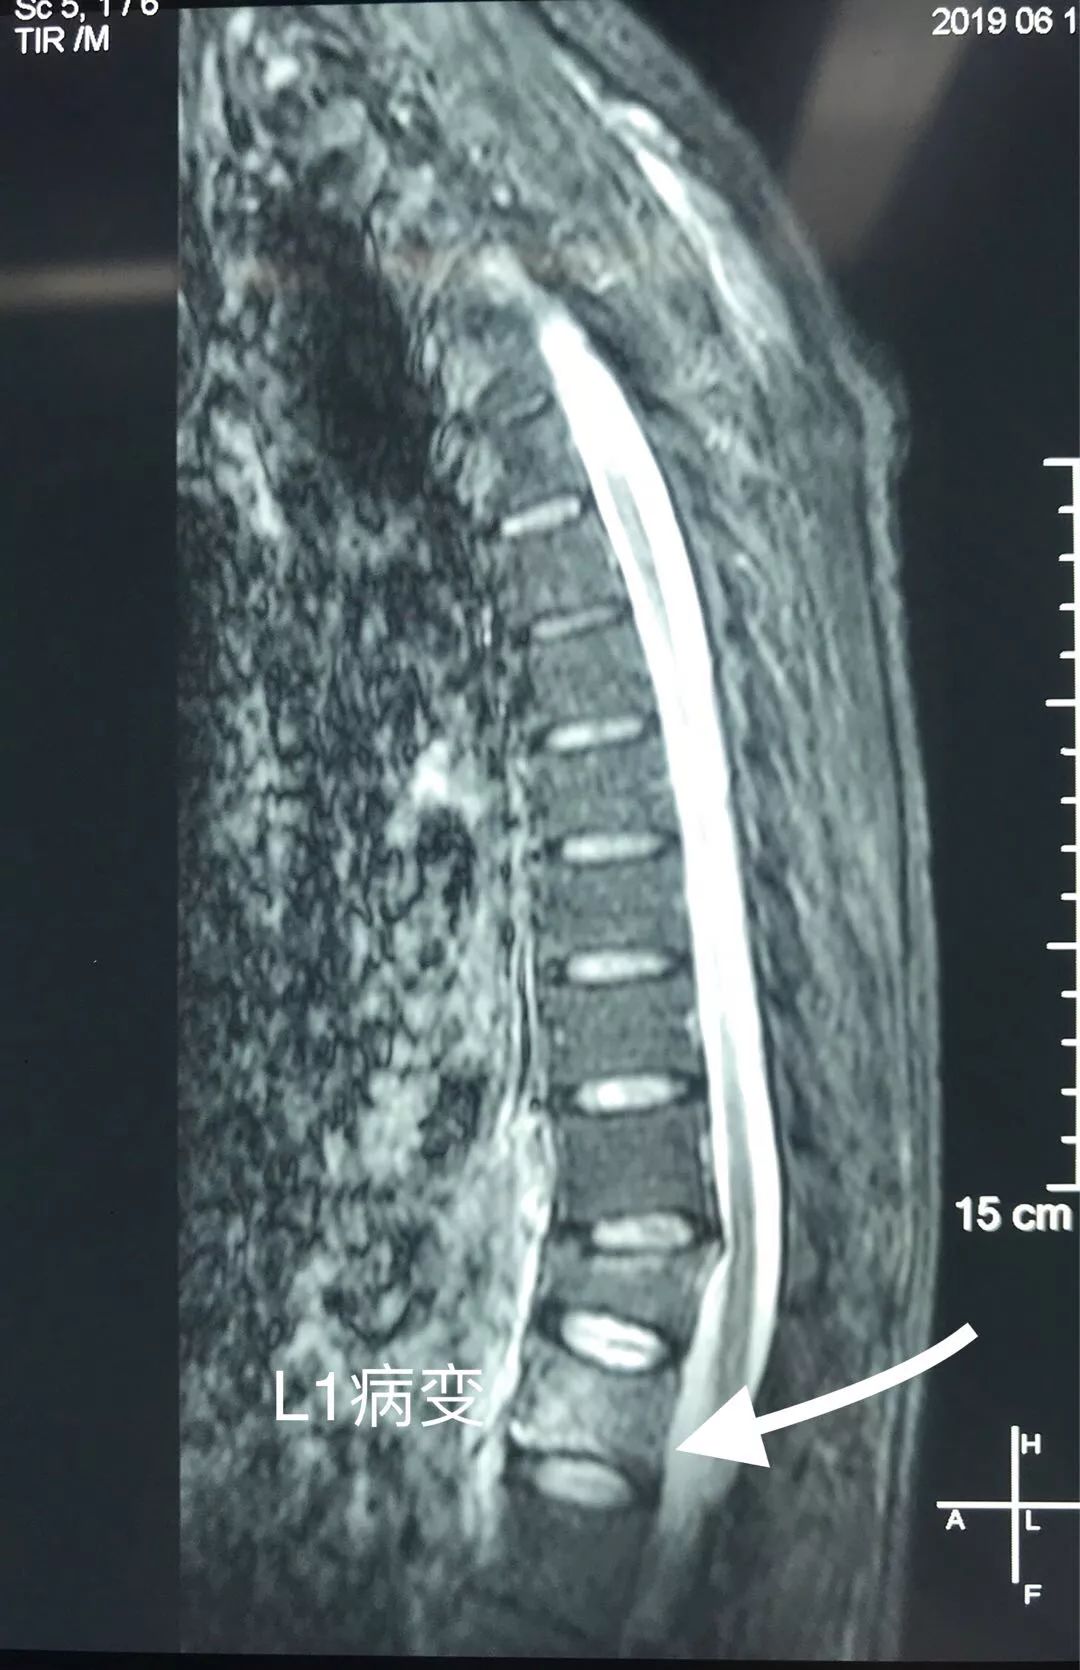

检查时发现,患者T12陈旧压缩性骨折,L1椎体新鲜骨折。但胸椎MR:T1加权象T1椎体呈弥漫性低密度改变,不同于一般椎体压缩性骨折的局限性水肿表现。

术前检查